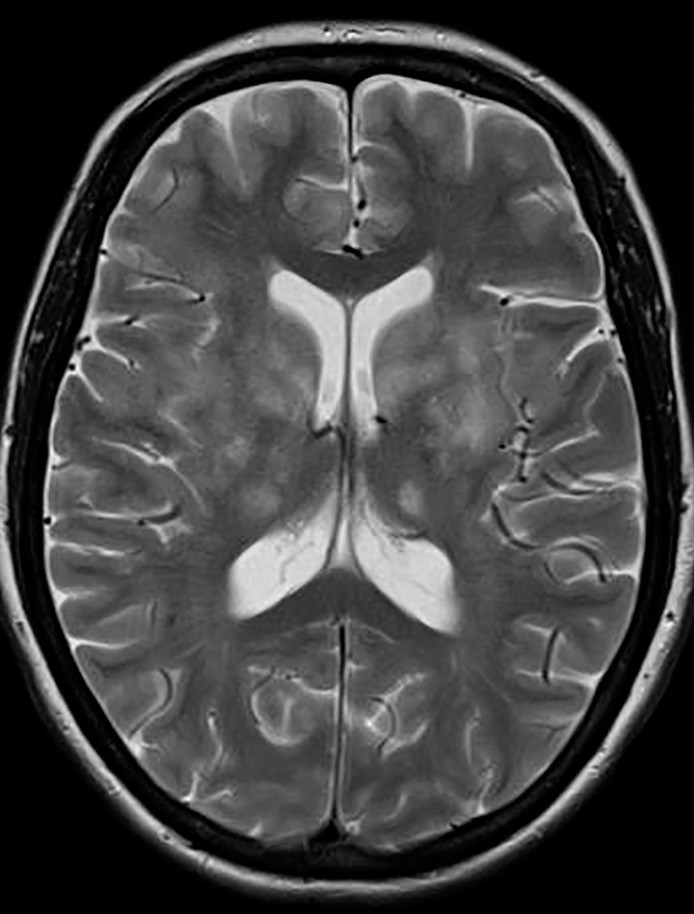

Som nevnt finnes det ikke spesifikke diagnostiske prøver for Behçets sykdom. Diagnosen må derfor stilles på bakgrunn av kliniske manifestasjoner der slimhinneulcerasjoner forekommer hos samtlige pasienter (5, 15). Hos ca. 60 – 70 % av tyrkiske og japanske pasienter med sykdommen finner man positiv HLA-B51 i serum (18,19). Prøven er positiv hos bare 10 – 25 % av europeiske pasienter. Spinalvæskeundersøkelse avdekker forhøyede proteiner og pleocytose, isoelektrisk fokusering er ofte negativ (5). Det er også rapportert om pasienter med kun forhøyet totalproteinnivå i spinalvæsken (11). Patergitest viser papulopustulært erytem 24 – 48 timer etter intrakutant stikk med en steril 21G-nål på underarmen. Denne testen er positiv hos halvparten av pasientene fra endemiske områder, men bare 10 – 20 % av pasientene fra Nord-Europa får positive funn ved patergitest (20). Ved den parenkymatøse formen av nevrologisk Behçets sykdom viser MR caput med T2-vektede bilder typisk hyperintense lesjoner i hjernestammen, spesielt mesencephalon, og i basalganglier (5, 14). Forandringer i hvit substans subkortikalt, frontalt og temporalt kan også forekomme (5). Lesjonene er ofte kontrastoppladende (14, 21).

Pasienter med myelitt har på T2-vektede MR-bilder hyperintense lesjoner som ofte strekker seg over 2 – 3 virvelhøyder. Disse kan likne på demyeliniserende forandringer. CT-angiografi av pre- og intracerebrale kar og konvensjonell angiografi viser fravær av typiske vaskulittforandringer (5).